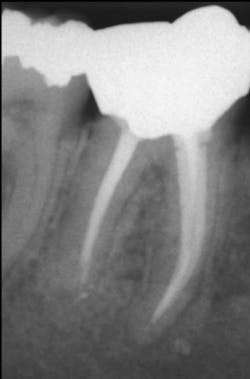

It is well known that all people perceive pain differently. Until you know the pain threshold of a specific patient, you cannot decide what level of analgesic to prescribe. The patient shown in Figures 1 and 2 had only an occasional awareness that there was movement in the grossly diseased mandibular molar tooth, while the patient with radiographically adequate endodontic treatment on a lower molar shown in Figure 3 was in constant pain, which interfered with his daily work. Pain threshold is obviously different from patient to patient. Dentists soon learn the pain thresholds of their patients.

Mild-to-moderate pain (Figure 3)

Figure 3: Patient with apparently adequate endodontic treatment in mandibular molar who complained of moderate pain constantly.